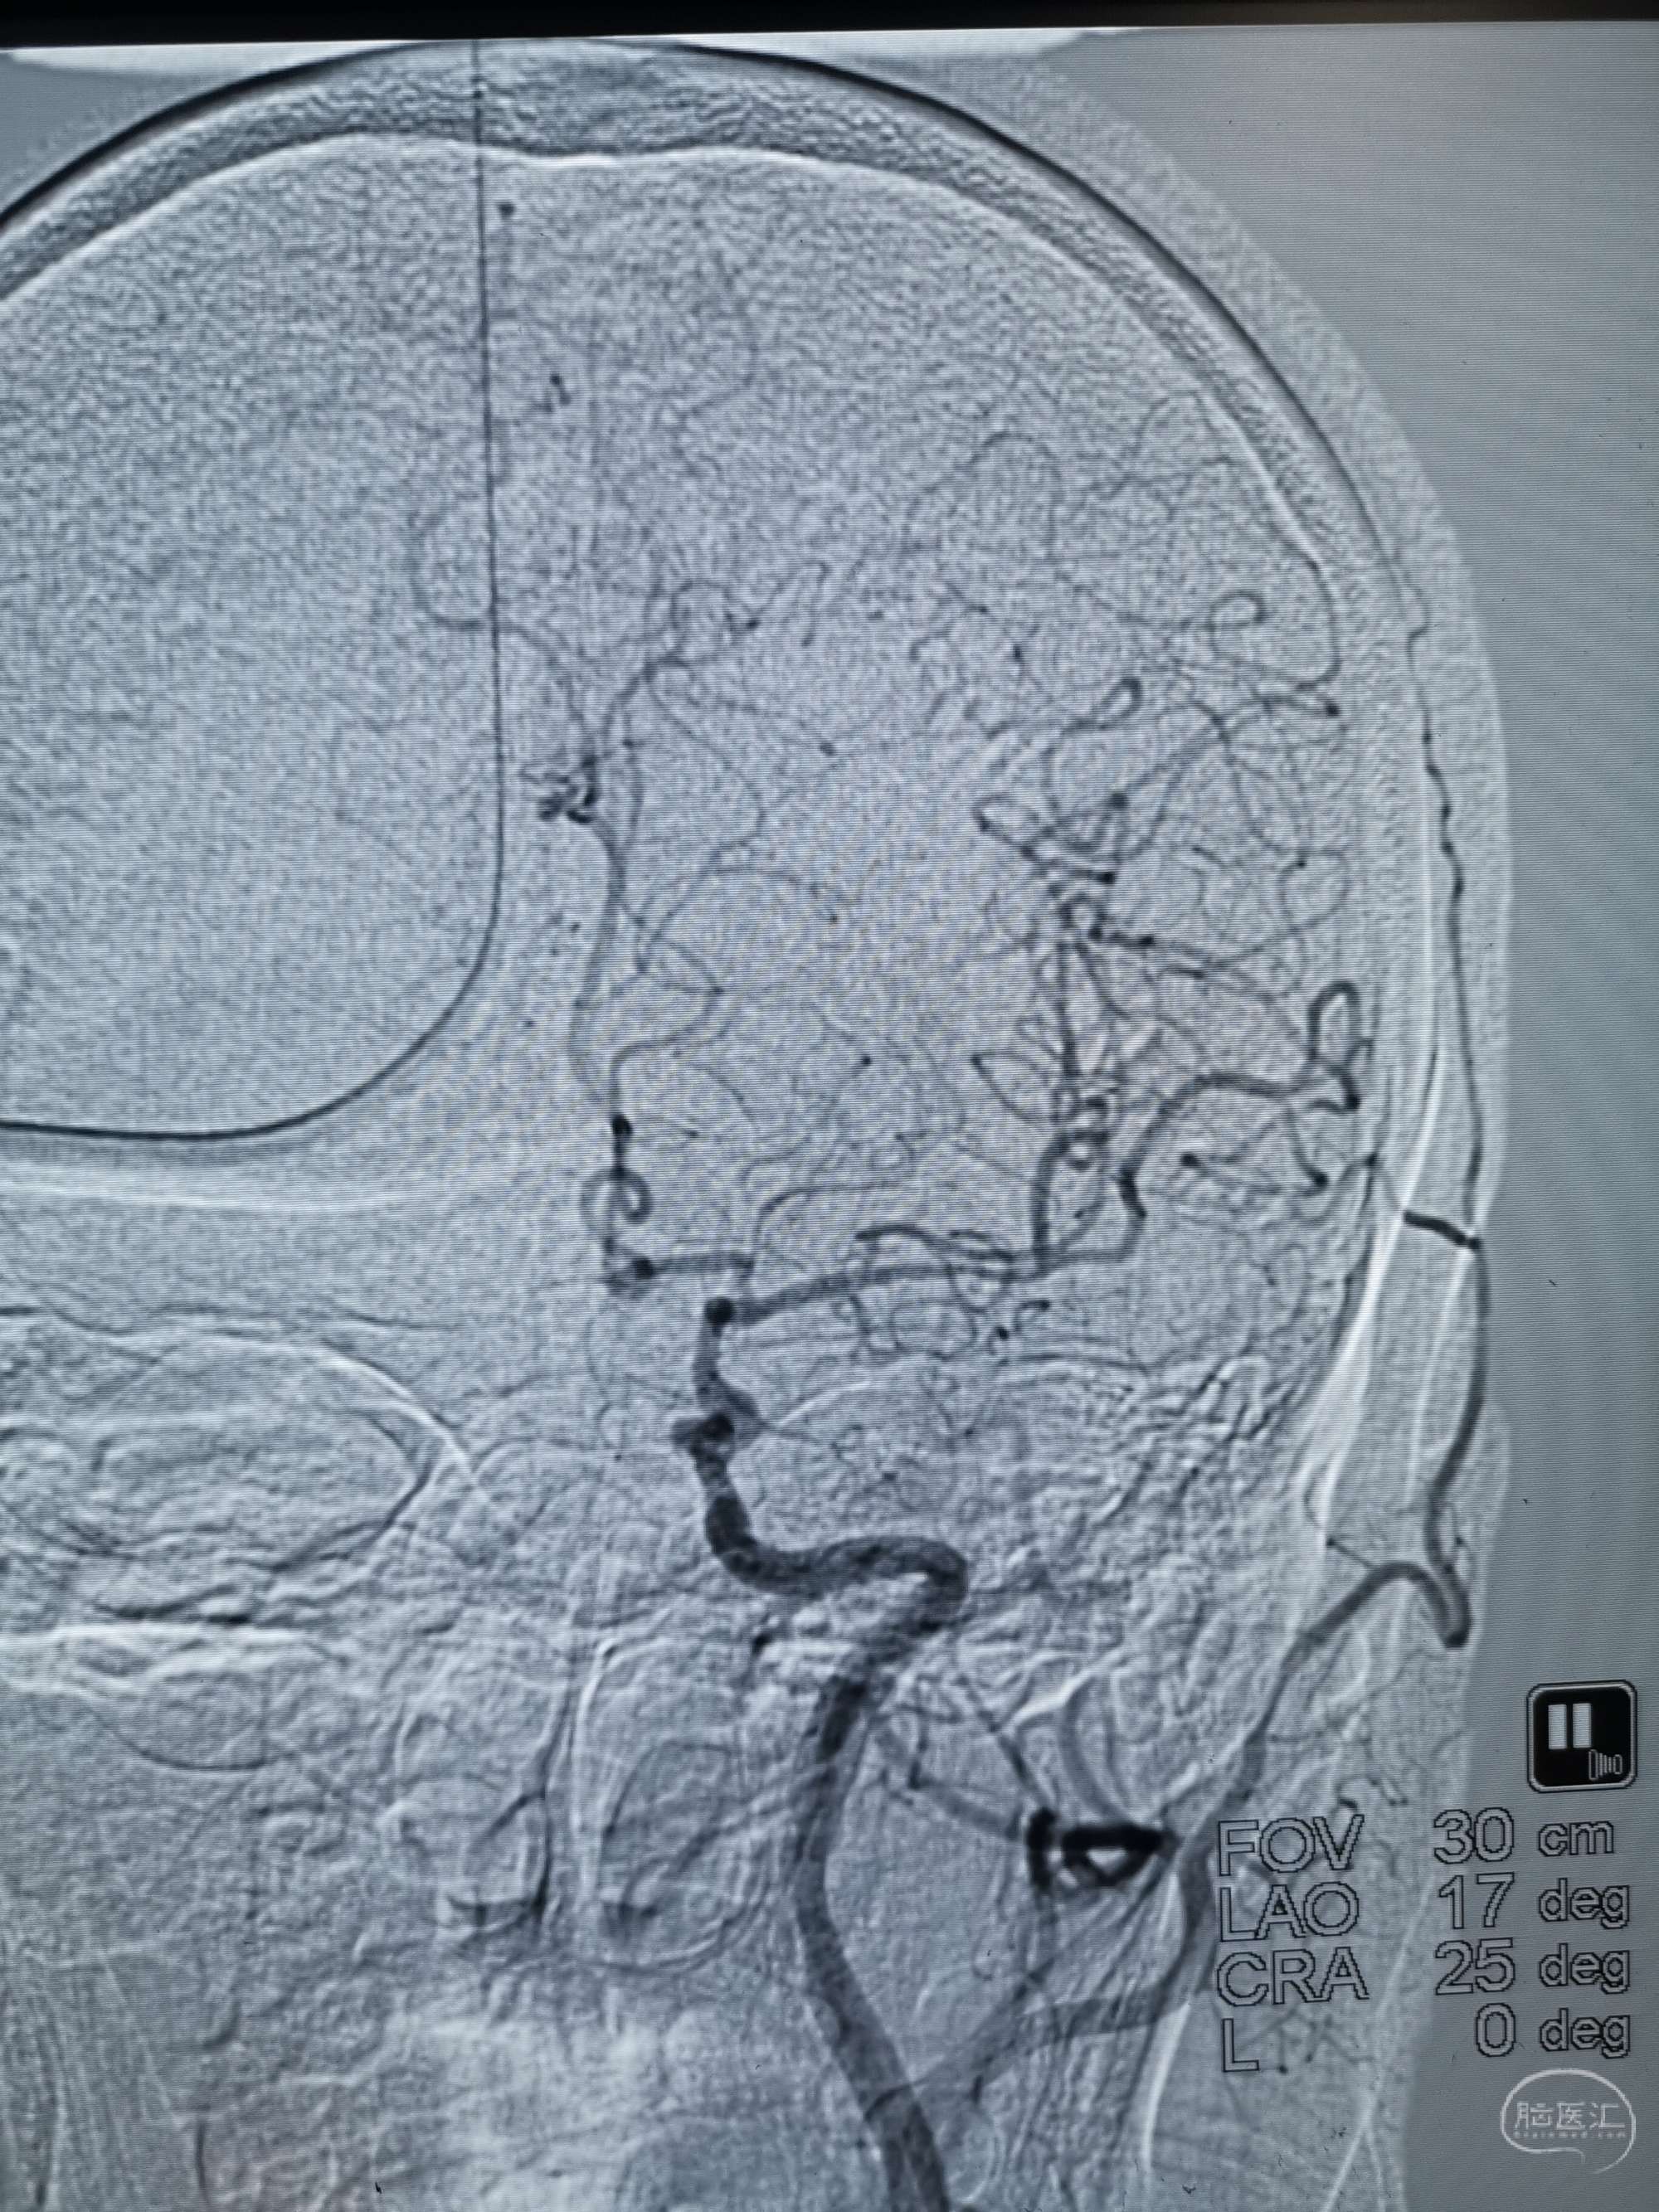

术前再次造影评估

右侧椎动脉穿支供血及左侧PICA供血较入院时略有改善,但改善不明显。故按计划行左侧椎动脉再通术